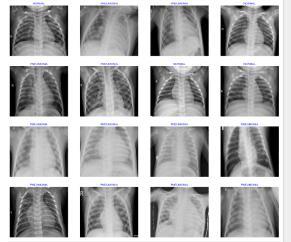

Thedatasetusedinthisprojectcomprised5216CXRdataset gotfromKaggle.Theseimagesweremeticulouslycuratedto includebothnormalandpneumoniacases,witheachimage annotatedtoindicatethewhetherpatienthaspneumoniaor Normal.Thediversityandrichnessofthedatasetallowedfor comprehensive training and evaluation of the pneumonia detectionsystem

WegothroughapproachofEfficientNetB3todetectanalysis x-ray.ThisincludedconvertingtheimagesformattoJPEGor PNGformat,enablingseamlessprocessingandintegration with deep learning frameworks. Additionally, the images were standardized to a predefined size and resolution, typicallysetto224x224pixels,usingrobustlibrariessuchas OpenCVorPIL.Normalizationofpixelvalueswasperformed to scale the intensity range to [0, 1], thereby enhancing consistencyandnumericalstabilityduringmodeltraining

CNNswerethecoreofourautomatedpneumoniadetection system.OurCNNdesignincludedlayersthatdetectdifferent featuresinchestX-rayimages,likeedgesorshapes,andthen poolthemostimportantinformation.Thisprocesshelpedus extractimportantfeaturesfromtheimages,makingiteasier to spot signs of pneumonia. Subsequent fully connected layersandactivationfunctionsfacilitatedtheclassificationof imagesintonormalandpneumoniaclasses,Inceptionwere fine-tuned to expedite model convergence and enhance performance.Thisstrategicapproachallowedforefficient utilizationofexistingknowledgeandresources,leadingto improvedmodelaccuracyandefficiency